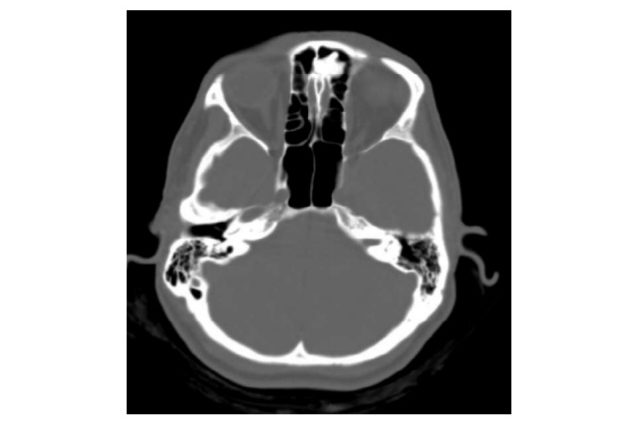

Gjate karieres profesionale ka kryer me mije vizita mjekesore dhe rreth 10 mije nderhyrje kirurgjikale te planifikuara dhe urgjente: hunde, sinuse, fyt, qafe, vesh, fytyre. Pervec nderhyrjeve kirurgjikale rutine qe lidhen me patologji te ndryshme, prej 20 vitesh kryen nderhyrje kirurgjikale te sukseshme per qellime estetike ne hunde,vesh, fyture, bazuar ne teknika dhe metoda bashkekohore. Numri I operacioneve estetike llogaritet te kap shifren e rreth 4 mije.

Dr. Gjergji ka diagnostikuar e kuruar me dhjetra raste qe per periudha te gjata kohore nuk kane mundur te gjejne zgjidhje megjithse ate e kane kerkuar kudo. Duke punuar prej nje kohe te gjate prane spitalit te traumes ka permiresuar ne menyre rrenjesore menyren e trajtimit te demtimeve ORL. Pervojen e fituar ne trajtimin e traumave e ka shfrytezuar dhe ne rastin e operacioneve funksionale dhe estetike te hundes duke lehtesuar apo hequr dore fare nga tamponimi post operator I hundes. Keto teknika kane permiresuar ndjeshen vuajtjet postoperatore duke i kthyer ne nderhyrje ambulatore me ecuri shume te mire postoperatore. Para disa vitesh kam futur konceptin e migrenes vertiginose, ky emertim po gjen cdo dite e me shume perkrahje nga opinion mjekesor shkencor nga gjithe bota. Ne opinion ka ndryshuar konceptin ne lidhje operacionin per zmadhimin e hundes pas traumave qe shoqerohej me asorbim te strukturave te quajtur “Agumentatio Rhinoplasti’. Per gjate gjithe kesa periudhe ka fituar eksperjence shume te mire ne trajtimin e dhimbjeve te kokes, marrjeve mendesh, uljen e degjimit zhurmen ne vesh, dhimbjet e fytit , ngjirjen e zerit, trajtimin e gerhitjes, etj.